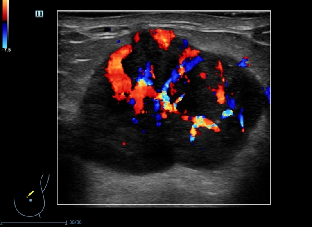

5类高度可能恶性,恶性的危险性≥95% 5类就是超声有≥3项恶性征象,几乎可以肯定为恶性

临床处理建议 超声引导下粗针穿刺活检并通过临床全面评估是否可以手术 提醒 #不疼的结节其实更危险! 如发现乳腺结节,有以下两种情况需要定期复查: 一是在短期内增大; 二是有乳腺癌或卵巢癌家族史者。 有些人觉得不疼不痒的肿块,就不当回事,其实有些没有症状的结节更危险,所以要强调复查。特别是>40岁以上的结节都要更谨慎,遵医嘱多复查。